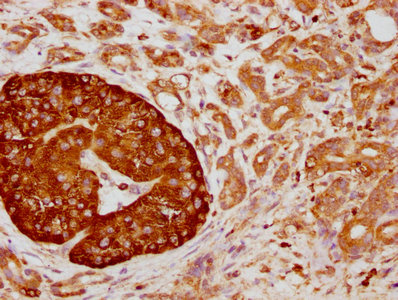

IHC image of CSB-RA004950A0HU diluted at 1:155 and staining in paraffin-embedded human pancreatic cancer performed on a Leica BondTM system. After dewaxing and hydration, antigen retrieval was mediated by high pressure in a citrate buffer (pH 6.0). Section was blocked with 10% normal goat serum 30min at RT. Then primary antibody (1% BSA) was incubated at 4℃ overnight. The primary is detected by a biotinylated secondary antibody and visualized using an HRP conjugated SP system.

IHC image of CSB-RA004950A0HU diluted at 1:155 and staining in paraffin-embedded human liver cancer performed on a Leica BondTM system. After dewaxing and hydration, antigen retrieval was mediated by high pressure in a citrate buffer (pH 6.0). Section was blocked with 10% normal goat serum 30min at RT. Then primary antibody (1% BSA) was incubated at 4℃ overnight. The primary is detected by a biotinylated secondary antibody and visualized using an HRP conjugated SP system.